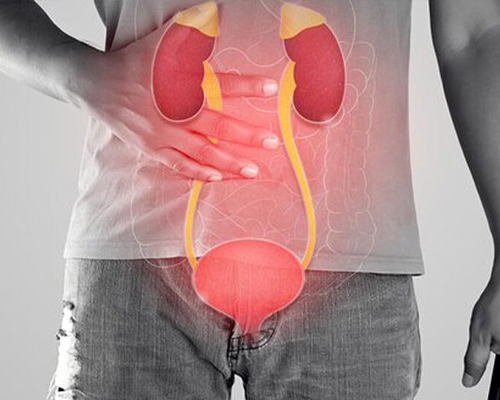

Kidney stone disease is a common urological condition in which hard mineral deposits form in the kidneys or urinary tract. These stones can cause severe pain, urinary obstruction, recurrent infections, and may lead to kidney damage if not treated on time.

He had extensive and grounded training in dealing with management of patients with kidney stone disease, urological malignancies, male sexual dysfunction, urethral stricture disease, prostate related disease and Renal transplant. His training also includes management of simple and complicated UTI, Urosepsis, Neurogenic Bladder, OAB, UAB, Renal Trauma, urinary incontinence, female Urology, Bladder pain syndrome.